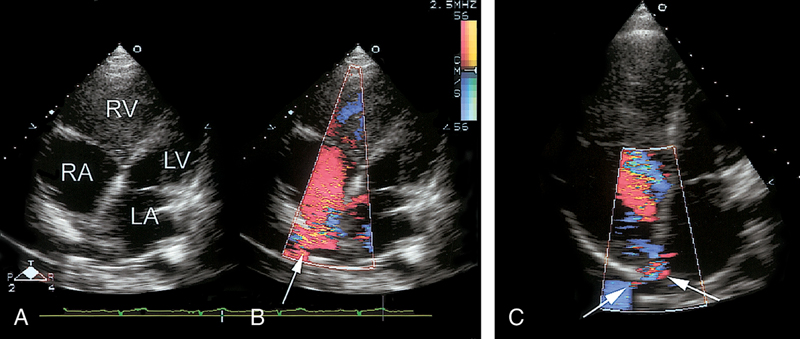

فحوصات تشخيصية لبعض امراض القلب والشرايين التاجية